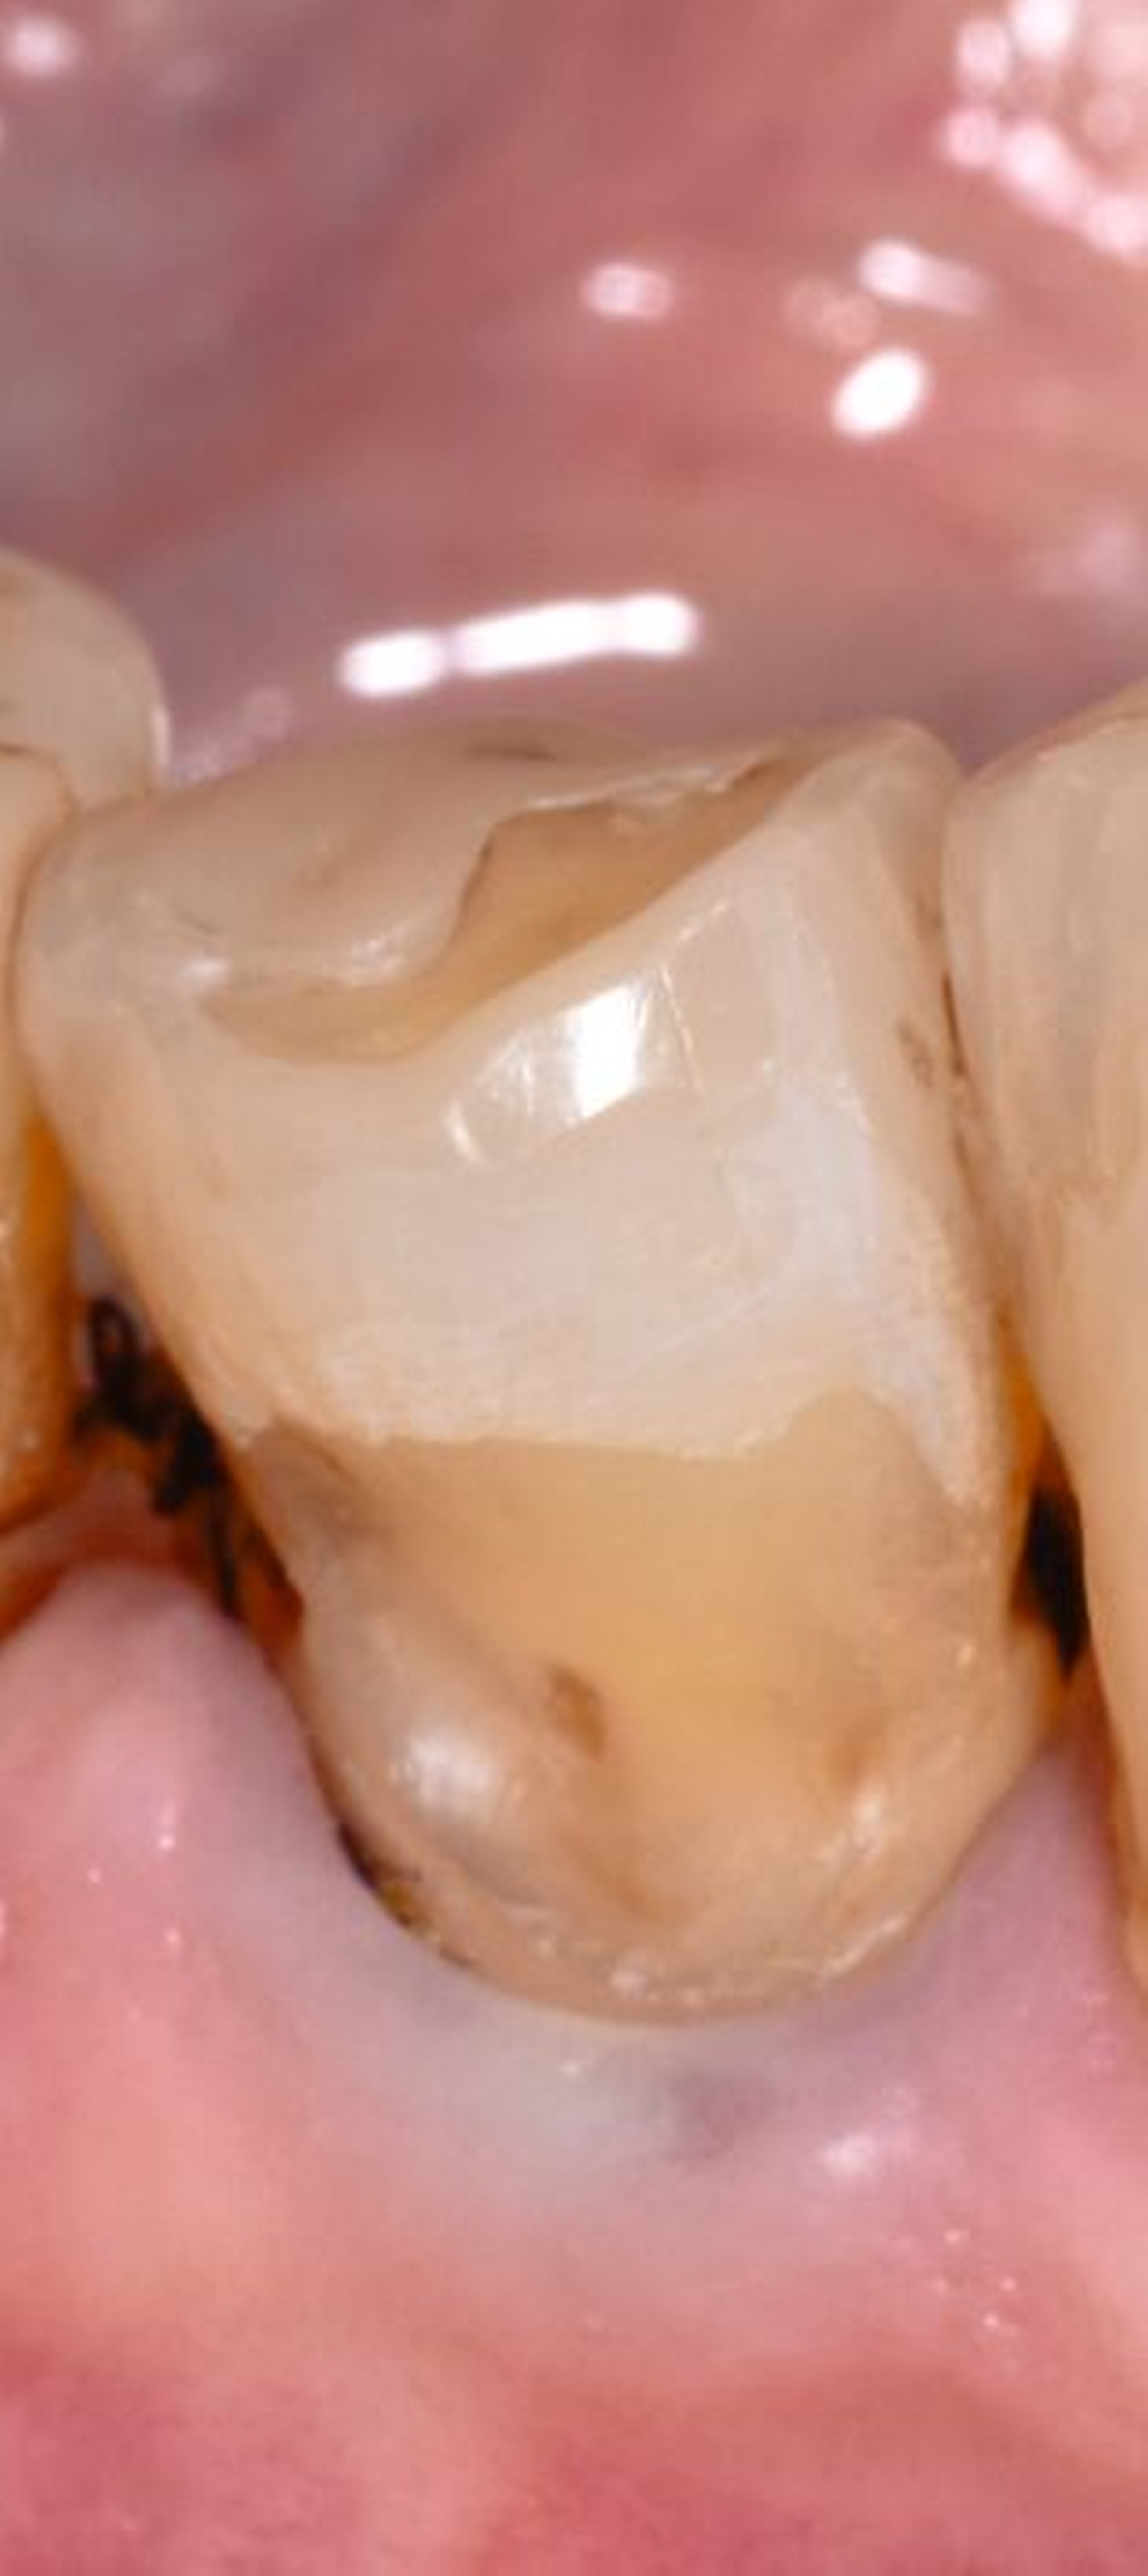

Die anschließende Ausarbeitung und Politur von Kompositrestaurationen ist erforderlich, um die Form der Restauration anatomisch korrekt zu gestalten, Überhänge, die einen Reiz für die umgebenden Weichgewebe darstellen können, zu entfernen und die Oberfläche zu glätten und somit zu vergüten. Polierte Kompositoberflächen sind widerstandsfähiger gegen Alterungs- und Abnutzungsvorgänge in der Mundhöhle. Raue Kompositoberflächen fördern die Plaqueakkumulation (Abbildung 3) und somit die Verfärbungstendenz des Materials. Die Glanzretention ist jedoch limitiert und je nach Ausgangsmaterial und Polierprozess unterschiedlich lang anhaltend.

Die Studienlage zur Politur erwies sich insgesamt als limitiert. Die inkludierten Studien [Jang et al., 2017; Nassar et al., 2014] wiesen zwar methodische Schwächen auf, ließen aber die Formulierung einer konsensbasierten Empfehlung zur Durchführung einer Politur zur Oberflächenvergütung und zur Reduzierung der Plaqueanlagerung zu. In Bezug auf die Auswirkung einer Politur auf das längerfristige Überleben oder Versagen besteht allerdings eine Forschungslücke, so dass dazu keine Aussage gemacht werden konnte.